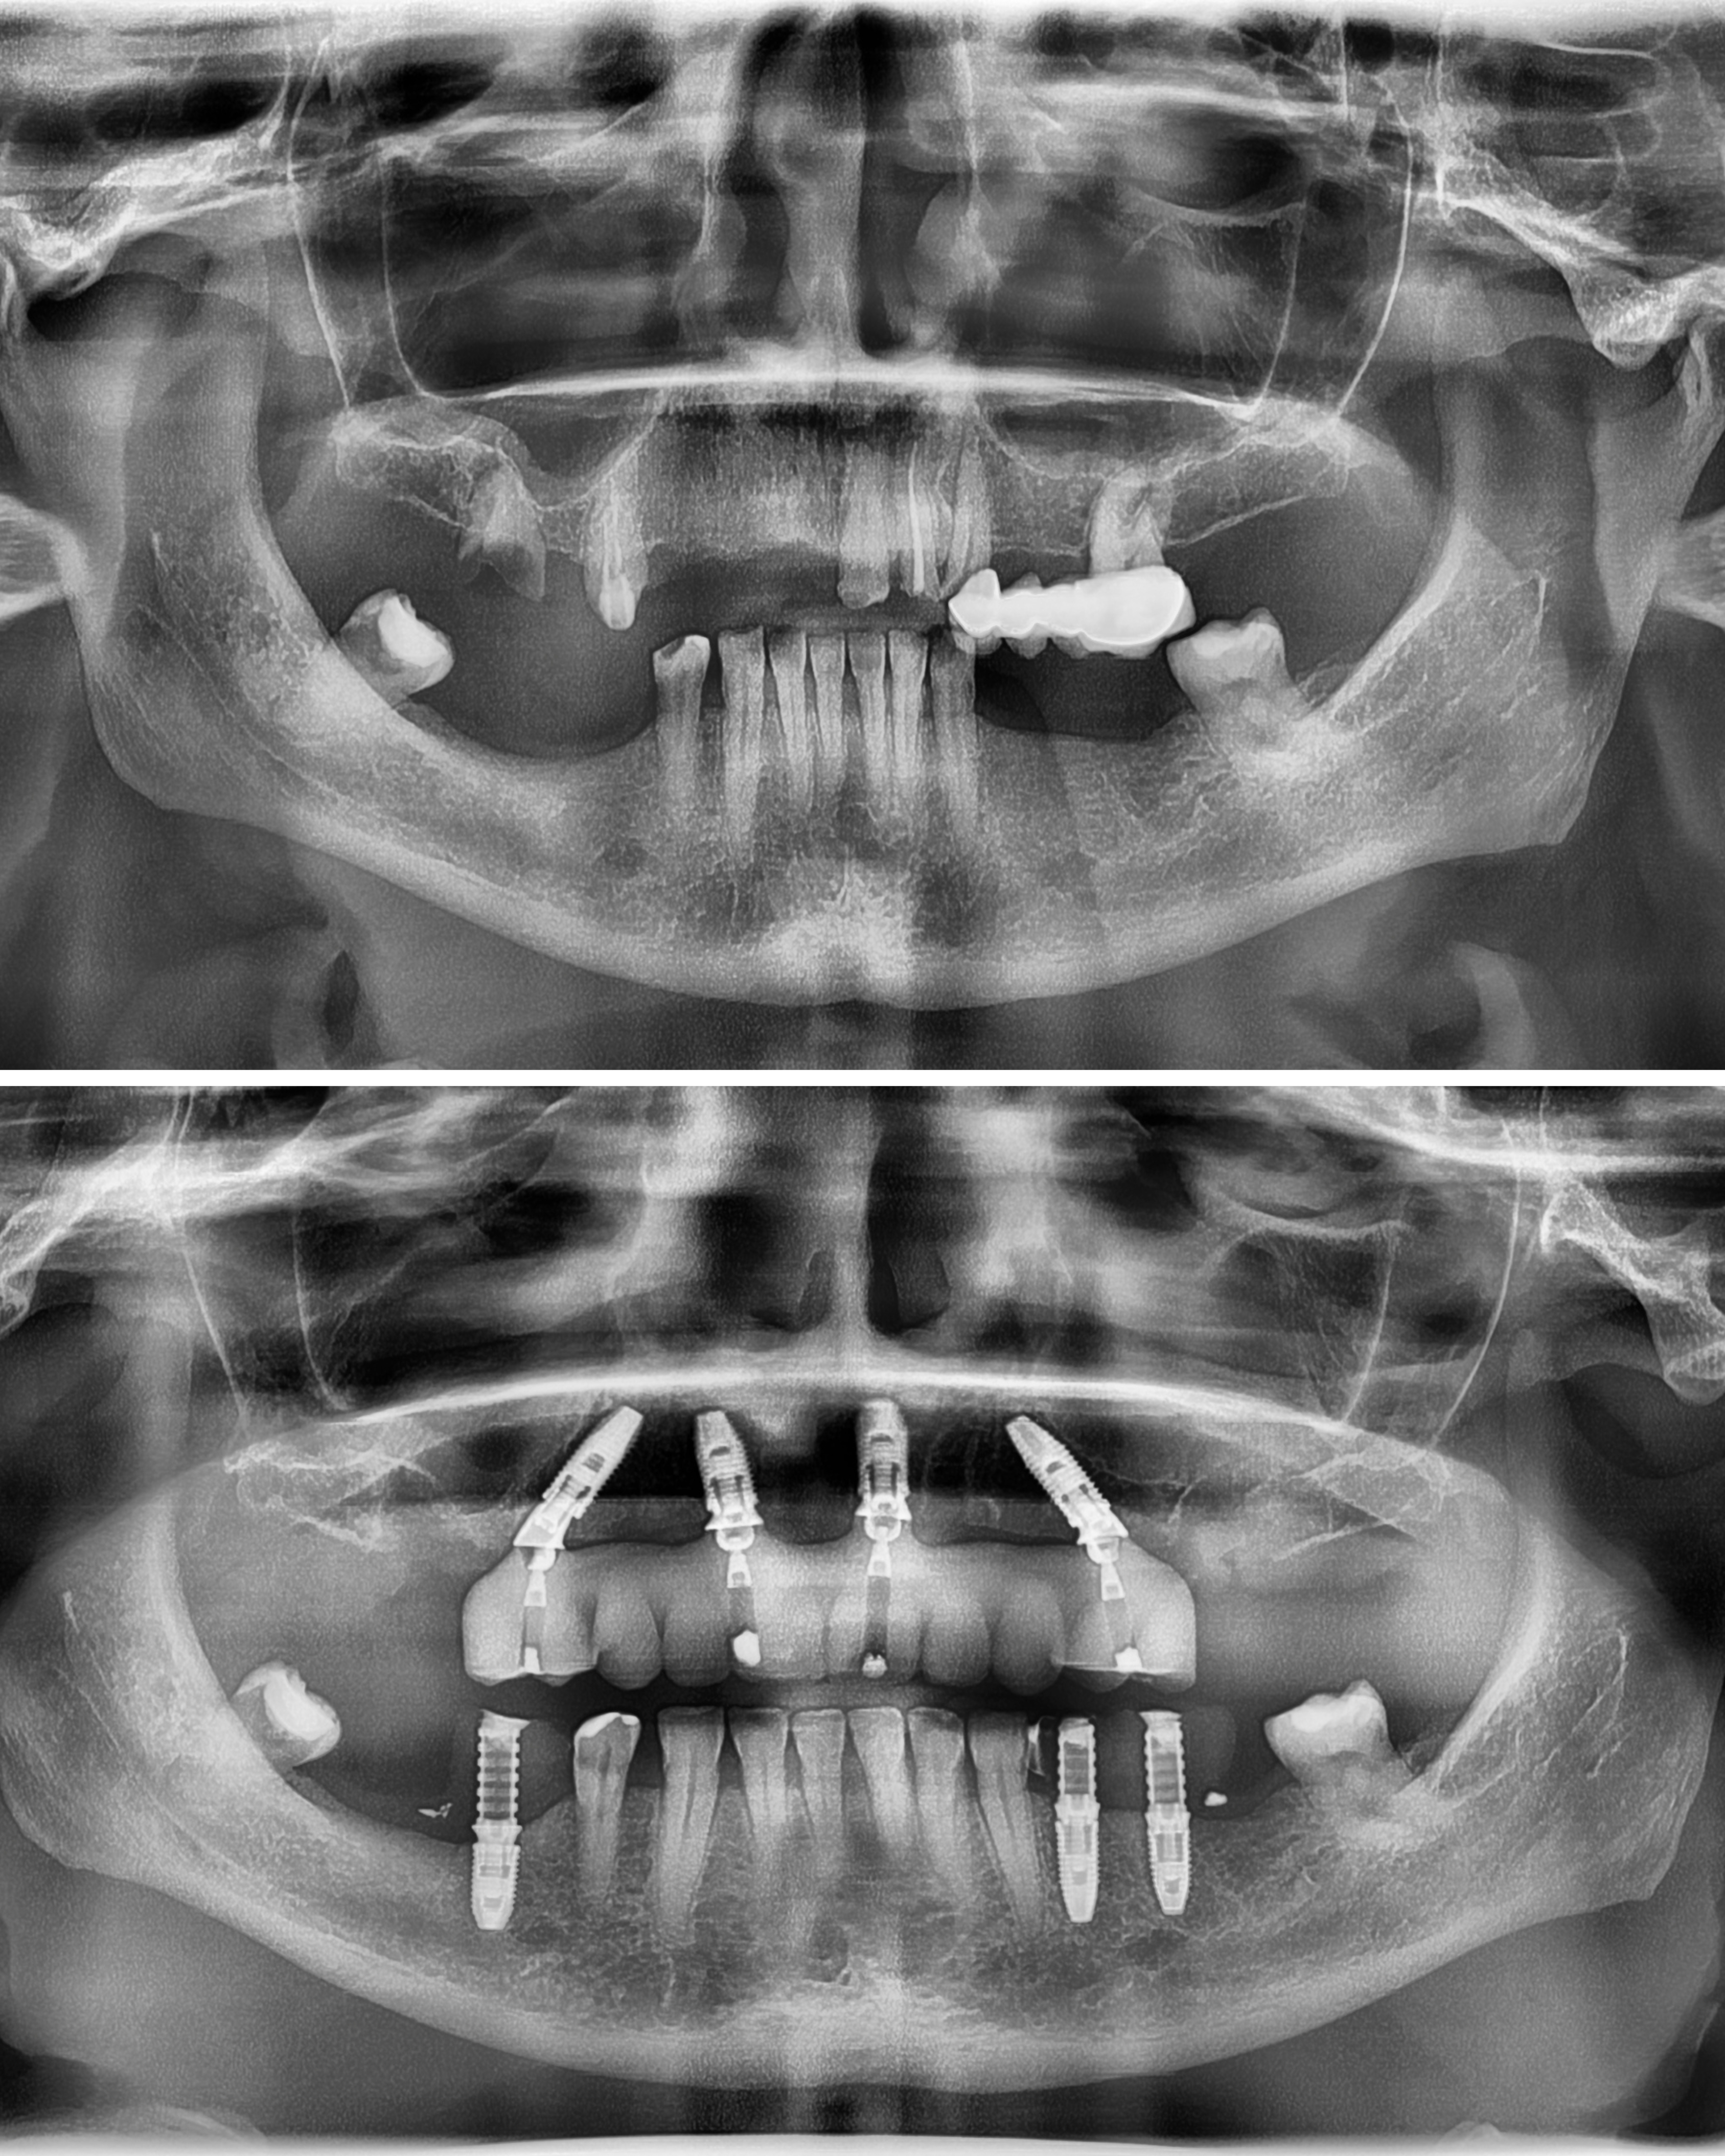

Po konsultacji w MALO CLINIC Warszawa i wykonaniu pełnej diagnostyki Pani Joanna została zakwalifikowana do leczenia metodą Malo Clinic Protocol.

To nowoczesne rozwiązanie pozwala na odbudowę całego łuku zębowego w jeden dzień – bez konieczności przeszczepu kości.

Zespół specjalistów MALO CLINIC przeprowadził zabieg metodą Malo Clinic Protocol, obejmujący usunięcie zębów nienadających się do leczenia, wprowadzenie czterech implantów oraz zamocowanie stałego mostu tymczasowego MAAB (Malo All Acrylic Bridge™ tego samego dnia. Cały proces wykonano z wykorzystaniem technologii cyfrowej – fotogrametrii, planowania komputerowego i druku 3D – co zapewnia maksymalną precyzję i naturalny efekt odbudowy.